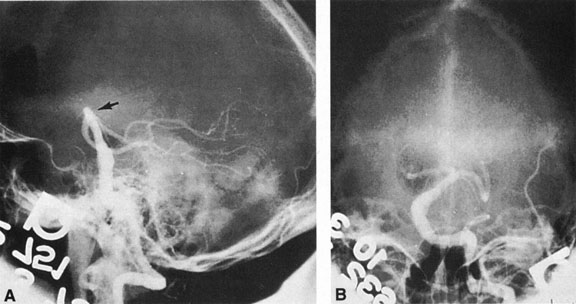

Vertebrobasilar System

Tortuous or redundant basilar arteries are not uncommon in the older age group. Occasionally, gross dilation or ectasia develops so that the basilar artery acts as a mass in the posterior fossa. This phenomenon produces signs of low-pressure hydrocephalus, cranial nerve palsies, and long tract and sensory signs and may even simulate a cerebellopontine angle tumor or tumor at the foramen magnum.58 It is possible to diagnose such lesions with CT59 or MRI60 but angiography is definitive (Fig. 6). The association of insidious multiple cranial nerve palsies and long tract signs referable to a brainstem level, in an elderly patient with evidence of atherosclerosis, should make fusiform basilar artery dilation a diagnostic consideration.

Fig. 6. Fusiform basilar dilation. A: Lateral projection vertebral arteriogram showing a widened basilar artery (arrow) projecting beyond level of dorsum sellae. B: Anteroposterior projection showing a widened and tortuous basilar artery.

As opposed to saccular basilar aneurysms, fusiform aneurysms tend to occur in the older age group (older than 60 years) and are found predominately in men.2,36 They are commonly associated with hypertension and atherosclerotic cardiovascular disease, and a notable association with abdominal aortic aneurysms also exists.